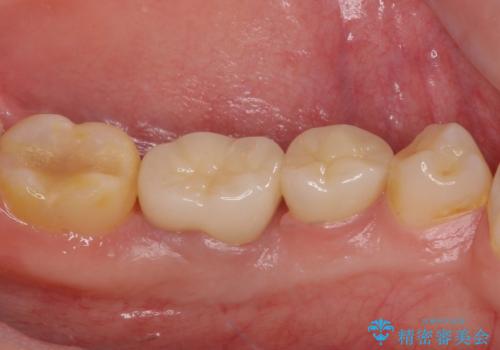

根歯の挺出(歯を引っ張り出す部分矯正)、歯周外科処置などを行った後、オールセラミッククラウンにて補綴することとしました。

当初は歯肉が腫れ上がり、大変不快な思いをされていましたが、セラミッククラウン装着後は清掃性が著しく改善し、患者様には大変満足していただきました。